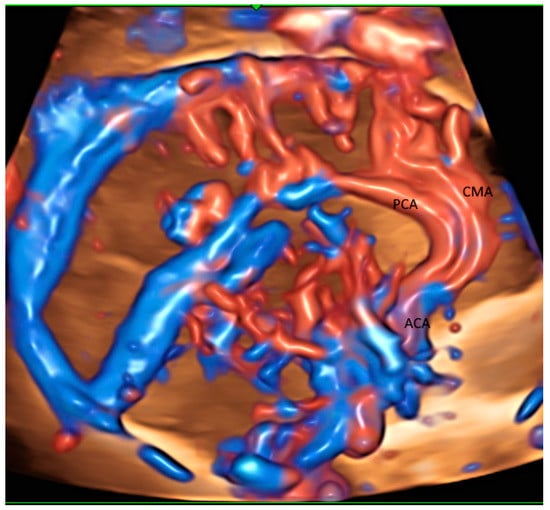

2.2. Brain

| Brain | Circle of Willis | Pericallosal artery Circle of Willis | Medullary veins and other small vessels |

| Brain | Pericallosal artery (HDFI) | GBM | Altered callosum development in FGR |